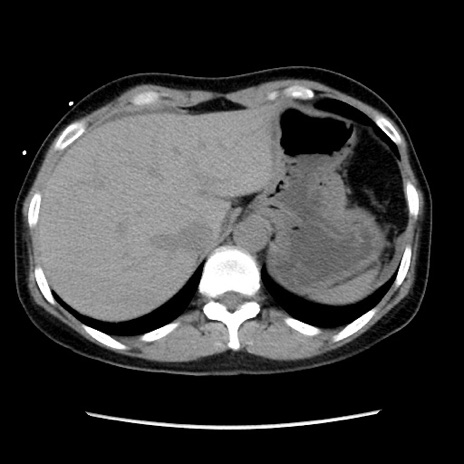

矢状断像

【症例】 50歳代女性

【主訴】 腹痛

【現病歴】前日生レバーを食べた。今朝に排便あり。 昼前に突然発症の腹痛を生じ、当院救急外来を受診した。

【身体所見】 意識清明、腹部:平坦、軟、下腹部やや左を中心に圧痛・反跳痛あり、筋性防御あり